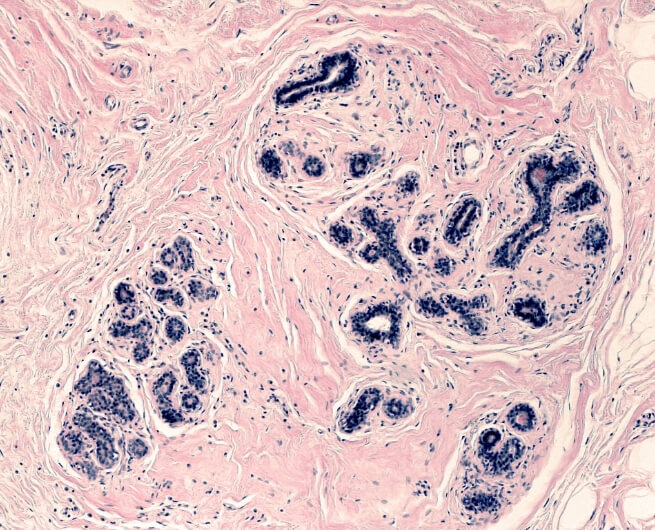

This buildup of fluid can cause skin changes such as hardening or “fibrosis“. The trapped fluid is a breeding ground for bacteria that can enter through cuts in the skin, creating an increased risk for infections like cellulitis.

What is Fibrosis?

Fibrosis feels like hard, thick tissue. The underlying factor? Insufficient movement of lymphatic fluid.